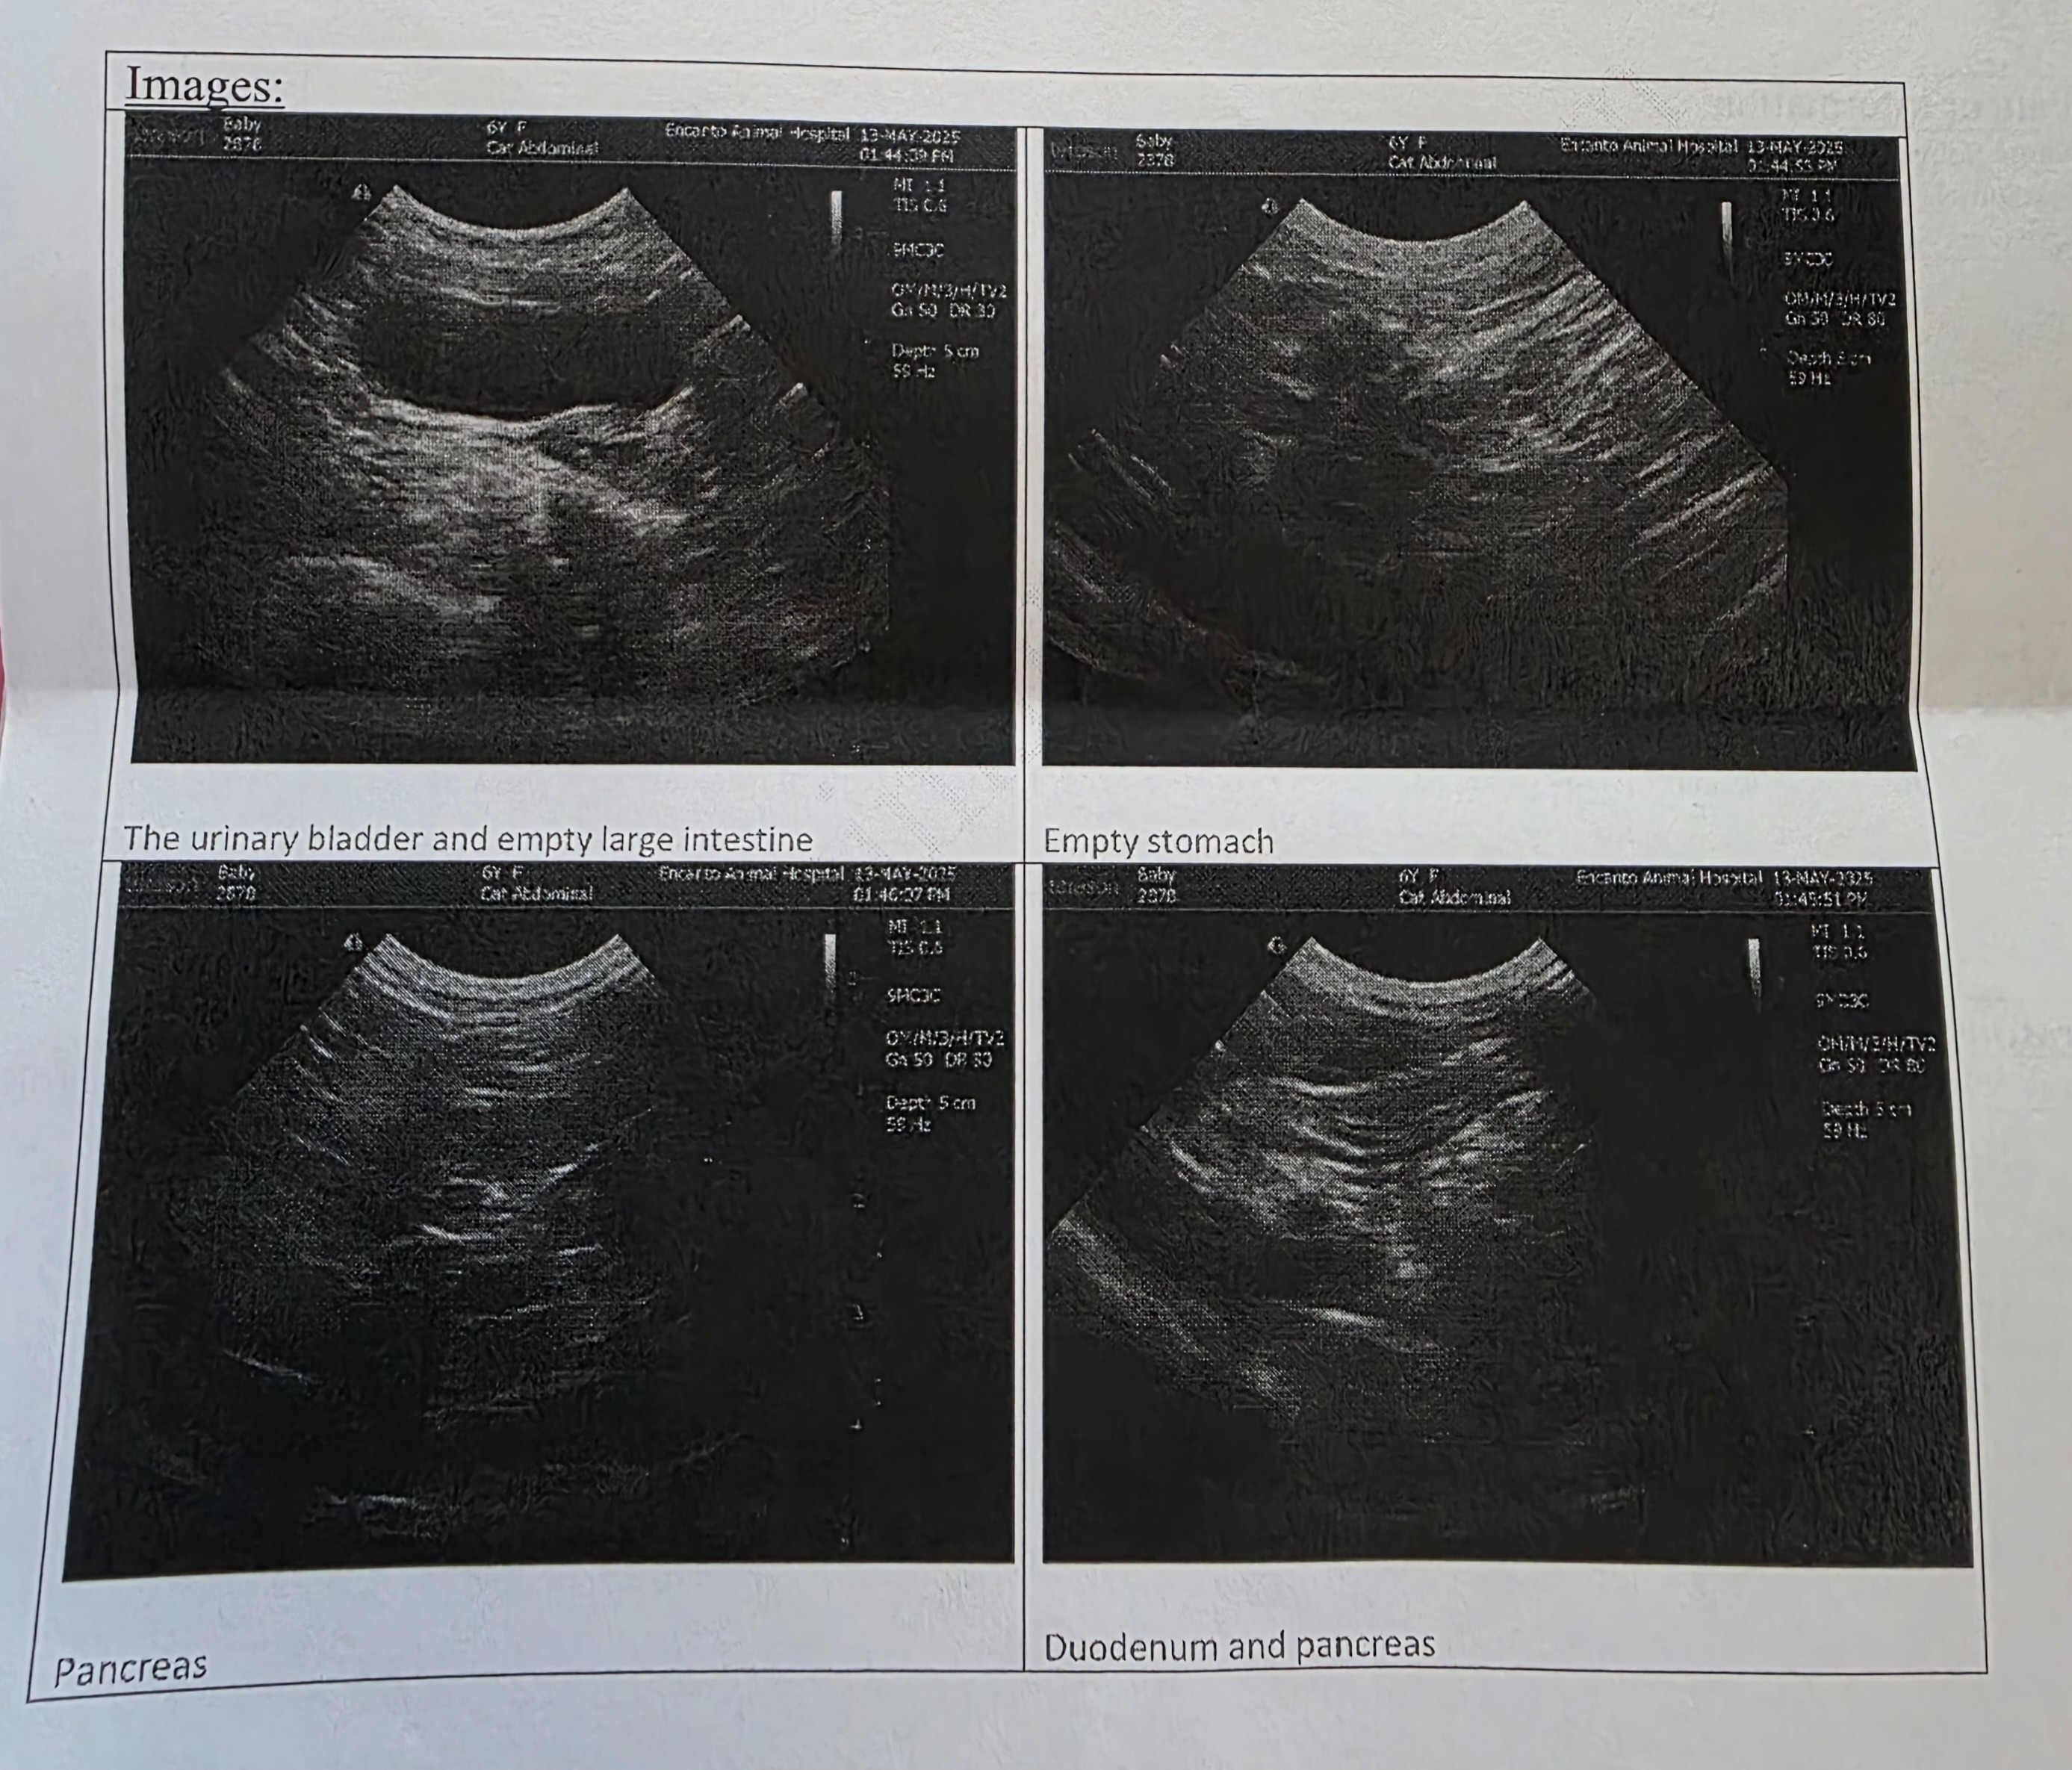

My sweet cat named Baby has been lethargic (not eating, not drinking water) and recently found that her GI tract is inflamed. Her vet wants her to see a specialist and get a biopsy, but the costs for these veterinary bills are just too high for me to cover at the moment. Possible illnesses could be IBD, lymphoma, or other illnesses which can't be diagnosed without a biopsy.